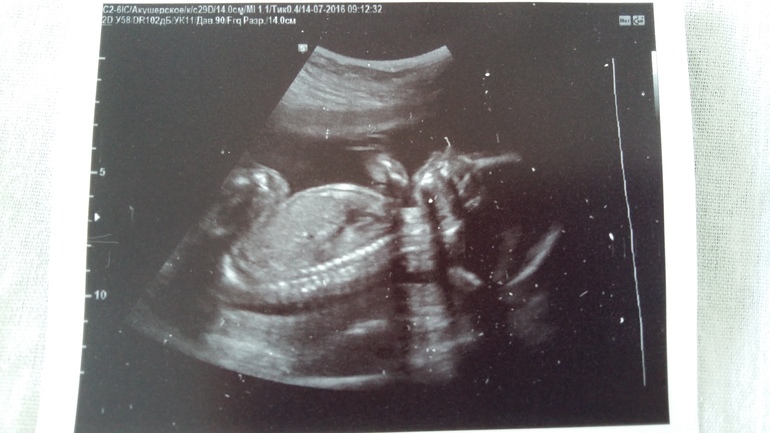

Сделали скрининг ровно в 20нед, наш сыночек Настенькой не стал) все соответствует сроку день-в день пока идем. Вес примерно 330гр был, окружность головки 18см

вот такой уже мой котенок, он с нами почти 5 месяцев! Как время то бежит)

Выглядишь отлично!))) малыш хороший, все косточки хорошо видно, тьфу тьфу))) хорошо тебе отдохнуть!)))

Привет!ты очень стройная,даже не догадаться что там такой уже большой малышок!спасибо.за фото узи,какие они хорошенькие уже на этом сроке,даже позвоночник виден жемчужной нитью.

Привет ) спасибо большое!!! Для меня каждое узи-как чудо какое-то. Так быстро подрастают, дивут в животике свокй жизнью прям ) с дочей немного другие были чувства, второй раз глубде что ли становятся)